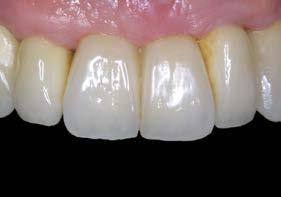

En una visión ampliada de la zona anterosuperior se aprecia la adecuada adaptación de los tejidos blandos a las coronas, lograda mediante la provisionalización y el diseño de pónticos y pilares que favorecen un contorno gingival armónico (Figuras 13 y 15).

Figuras 13 y 14. Imagen detallada de los perfiles de emergencia logrados, favorecidos por la fase de provisionalización y el diseño de pónticos y pilares.

La paciente continúa bajo seguimiento periodontal. A los 5 años se observa estabilidad clínica del tratamiento (Figuras 22–24), sin recesiones gingivales ni pérdida ósea asociada en las imágenes clínicas y radiográficas.

Un año más tarde, al finalizar el periodo de seguimiento (24 años), las fotografías intraorales evidenciaron ligeras alteraciones de los tejidos blandos, con pequeñas troneras abiertas,

más evidentes en los dientes naturales conservados que en las restauraciones implantosoportadas. A pesar de estos cambios, el resultado global se consideró satisfactorio desde el punto de vista funcional y estético, especialmente en comparación con la situación clínica y radiográfica inicial previa al tratamiento (Figuras 26–31).